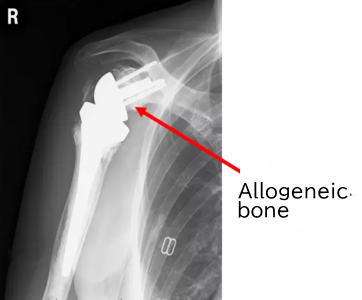

Postoperative X-ray

Therefore, a shaped allograft is attached to the baseplate to fit the deformed glenoid.

The baseplate with the allograft is fixed to the glenoid.

The glenosphere is attached.